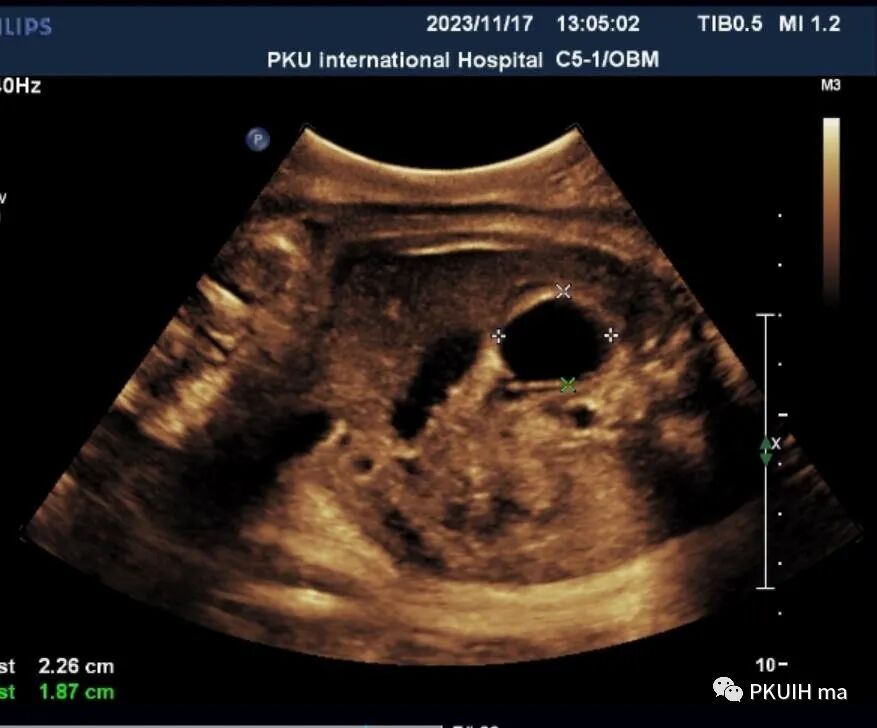

胎儿腹部囊肿在临床中是比较常见的,发生的部位有肝、胆道、肾、肾上腺、胃肠、卵巢、子宫及阴道等。在诊断异常时首先需要认识正常结构,因胎儿腹部内有许多结构表现为囊性的。对于囊肿的诊断首先要确定囊肿发生的部位。肾上腺区囊性占位并不罕见,临床中最常见的就是肾上腺出血性囊肿、单纯囊肿或成神经细胞瘤囊性变。肾上腺区的囊肿相对于腹腔其它部位囊性占位的鉴别比较容易,下面看看几个病例孕妇之前超声检查均正常,于38周发现右肾上极前内侧见一囊肿回声,大小约2.2x1.8cm,囊内透声好,其内未见血流信号。囊肿下方似见部分肾上腺组织。生后超声检查考虑肾上腺囊肿,随访至六个月囊肿无变化。新生儿目前无异常,一直在定期随访中。